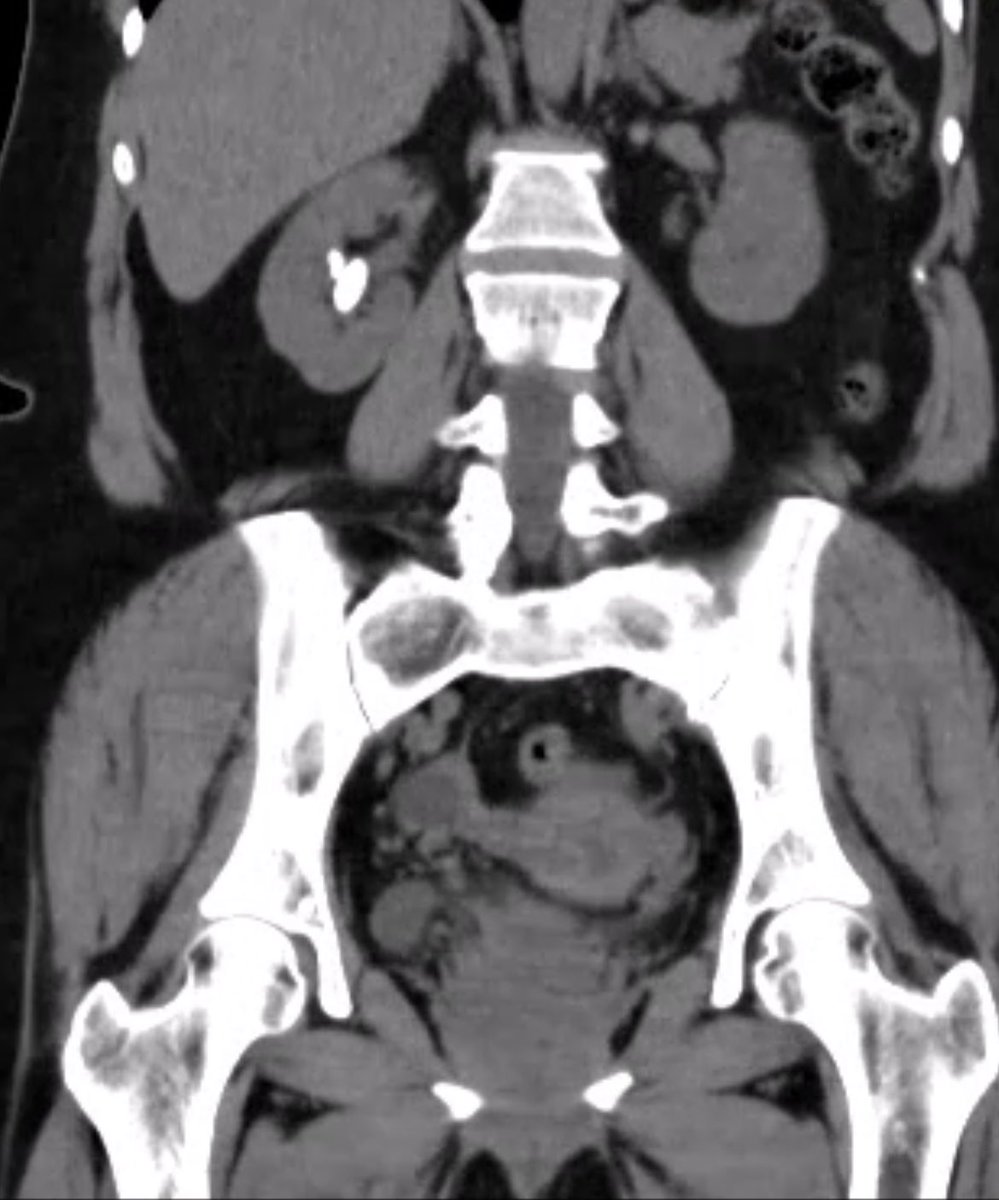

MINIECIRS con técnica biplanar 0-90 modificada, la escuela del Dr @urobraulio en Gdl en el famoso hospital Zoquipan, muchas gracias por la enseñanza y la oportunidad @endourojimenez @endouropat